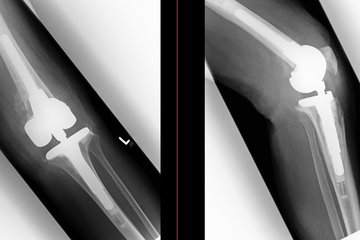

Knieendoprothetik mit Teil- oder Totalendoprothese

Selbstverständlich gehen wir bei der Behandlung der Gonarthrose zunächst immer vom kleinstmöglichen Eingriff aus. Wenn alle konservativen Behandlungsmöglichkeiten ausgeschöpft sind, kommt bei einem stark ausgeprägten schmerzhaften Verschleiß des Kniegelenkes (Arthrose) nur noch die Implantation eines künstlichen Kniegelenkes, einer Endoprothese, infrage. Je nach Ausmaß und Lokalisation der Arthrose können dabei evtl. nur einzelne Anteile des Kniegelenkes (Schlittenprothese, femoropatellarer Ersatz) oder das ganze Gelenk (bimopartimenteller Ersatz) operativ ersetzt werden.

Mit tausenden vollzogenen Operationen im Bereich der modernen Endoprothetik stellt unser Team Ihnen das komplette Spektrum des Teil- oder Totalersatzes bereit. Je nach den persönlichen Anforderungen unserer Patientinnen und Patienten besprechen wir gemeinsam, welche Lösung im individuellen Fall die beste ist, um ihnen zur gewohnten Lebensqualität und ihrem ganz persönlichen Aktivitätslevel zurückzuverhelfen. Dabei kommen ausschließlich gleichermaßen hochmoderne wie bewährte Prothesen namhafter Hersteller zum Einsatz. Gemeinsam mit Ihnen finden wir den besten Weg!